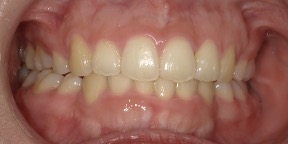

33歳女性のビフォーアフター

| 診断 | 空隙 |

| 治療方針 | 治療方針:前歯の咬合関係改善と空隙閉鎖を主な目的にて主にIPR(歯と歯の間をわずかに削合してスペースを獲得する方法)を組み込んだ動的矯正治療を行い、空隙、前歯咬合を改善後、保定を行う。臼歯部の咬合関係はプランの都合上維持することとした。 |

| 治療費 ※ | 67万8千円(診断、型取り、矯正中のメンテナンス、保定装置を含む料金) |

| 治療期間 | 6か月 |

| リスク | 1日20時間以上マウスピースを使用できない場合、歯が動かなかったり、想定しない誤差により不完全に終わる可能性がある。装着時や食事時に痛みを伴う。歯肉退縮や虫歯になるおそれがある。また、指導通りに装着できていない場合や適切なブラッシングが出来ていないとそのリスクが高くなる。歯根が短くなることがある。ごくまれに歯の神経が損傷してしまうことがある。過去にぶつけたり深い虫歯治療をしたことがあるとそのリスクはやや高くなる。矯正後には保定装置が必要。適切な使用ができない場合、後戻りの原因となる。将来的に歯並びが動いて再矯正が必要な場合がある。親知らずが正常に生えていない場合、その可能性がやや高くなる。 |

※ 治療費は、治療当時の費用で、現在の費用と異なる可能性があります。現在の費用は治療費のページでご確認くださいませ。